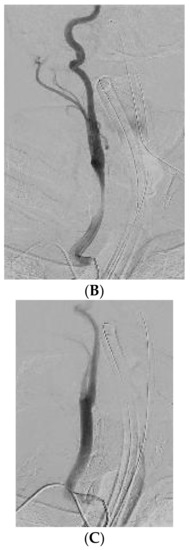

Emergency CT angiography confirmed that the catheter had transversed the internal jugular vein and had been inserted into the right subclavian artery. Ultrasound Doppler examination of the right upper extremity confirmed presence of a biphasic signal in the brachial radial and ulnar arteries. Following vascular surgical and interventional radiology consultation, intravascular balloon tamponade with concurrent external pressure application was decided as the preferred method for safe catheter removal. The patient was transported to the Interventional Radiology Unit, (Figure 1A) where an 8 × 40 mm Mustang angioplasty balloon (Boston Scientific, Marlborough, MA, USA) was inserted through the right brachial artery, which was immediately inflated after the CVC removal, providing internal balloon tamponade while simultaneous external pressure was applied to the insertion site for 5 min. Subsequent angiography revealed no leaks or fistulae (Figure 1B). No further complications from the accidental intra-arterial catheter insertion were noted. On the 18th day of ICU stay, the patient was discharged to the Neurology Department, with a GCS of 10/15 (Eye: 4/4, Motor 5/6, Verbal: 1/5) and neurological findings similar to those noted on hospital admission.

Figure 1. (A) CT angiography confirming right subclavian artery catheterization, just distal to the origin of the right vertebral artery. (B) Final result after removal of the CVC with no extravasation.